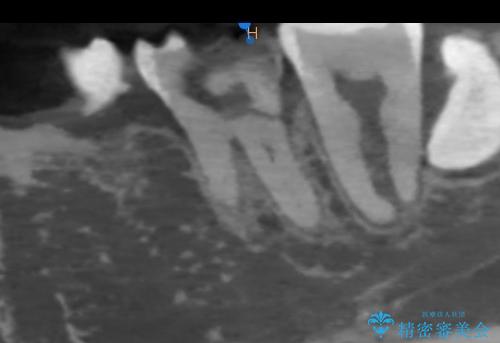

レントゲンやCTより、深くまで破折していることが分かり、抜歯が必要な状態でした。

歯槽骨の状態は良好であったため、抜歯即時埋入インプラントによる補綴治療を行うこととしました。